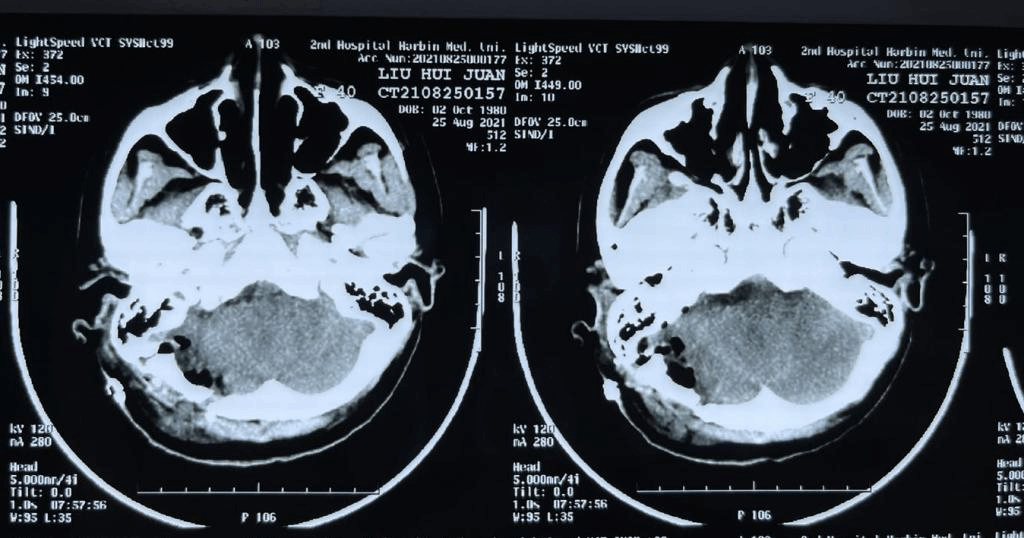

术前CT及磁共振

术后CT及磁共振